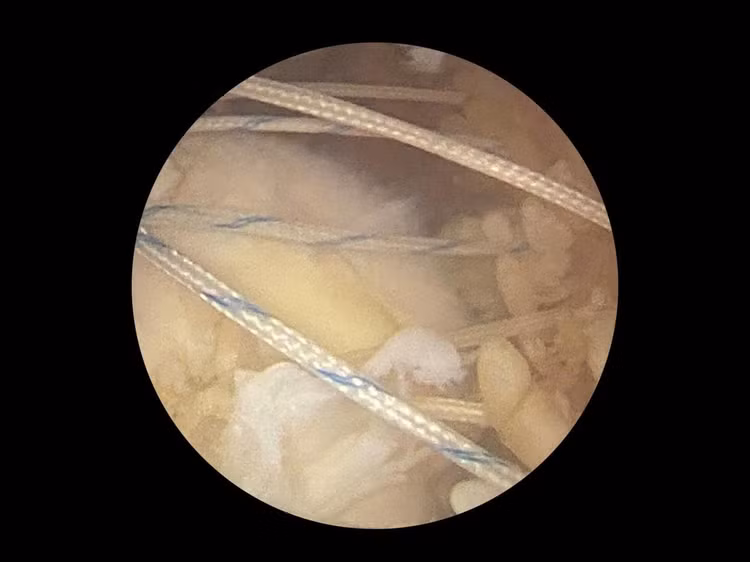

Gân rách trên vai được khâu bảo lại - Ảnh BVCC

Bệnh nhân được chẩn đoán: Chấn thương vai trái – Rách hoàn toàn gân trên gai, hẹp khoang dưới mỏm cùng vai. Sau hội chẩn chuyên khoa, bệnh nhân được chỉ định phẫu thuật nội soi khâu chóp xoay và làm sạch khớp vai – đây là phương pháp điều trị hiện đại, xâm lấn tối thiểu, giúp phục hồi cấu trúc gân và giảm đau hiệu quả.